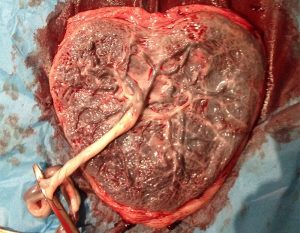

La placenta es un órgano que constituye el enlace de vida entre el feto y la madre al momento del embarazo. El termino placenta proviene del latín que significa “torta plana” por la forma que tiene este órgano en los humanos. Este órgano se desarrolla gracias a las mismas células que provienen del espermatozoide y del ovulo, las cuales también desarrollan el feto.

La placenta se comprende por el componente materno, que es la transformación de la membrana uterina y otra parte de origen fetal. La placenta principalmente tiene millones de vasos sanguíneos encargados de todas las funciones. Este órgano se implanta y se sujeta fijamente en la pared uterina, aunque eso no impide que cambie de posición dentro del útero ya que es como un globo que crece en el transcurso de la gestación.